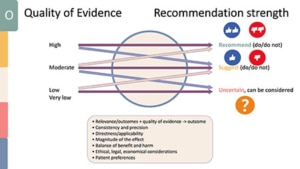

Voor de richtlijnen van de EFP wordt gebruik gemaakt van aanbevelingen. Dit kan zijn om iets wel of niet te doen, het te overwegen om wel of niet te doen of dat het onduidelijk is. Deze zijn gebaseerd op kwaliteit van bewijs sterk tot zwak en basis van een aantal overwegingen kan bewijs worden omgezet tot een aanbeveling.

Klik hier voor een vergrote afbeelding

De richtlijn van de NVvP richt zich met betrekking tot stap 1 op de inventarisatie van het niveau van zelfzorg, het begeleiden en optimaliseren van mondhygiëne en gedragsverandering. Het advies is om 2x per dag te poetsen met fluoridetandpasta. Patiënten willen vaak weten wat ze moeten doen, maar doen het vaak niet omdat motivatie vaak het probleem is.